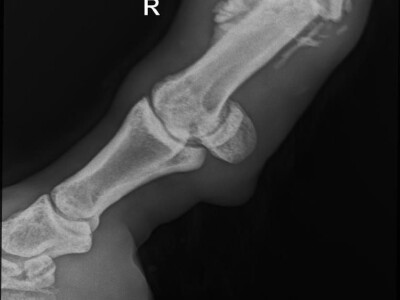

Godinama je vrijedno radio u masliniku, a onda se desila nezgoda – slomio je nogu. Rekli su „To je samo konj, a ne čovjek, za njega nije bolnica, nego klaonica“. Na sreću, zahvaljujući požrtvovnim ženama s Brača koje su pokrenule akciju spasa, taj se crni scenarij, za malog bijelog konja, ipak nije ostvario.